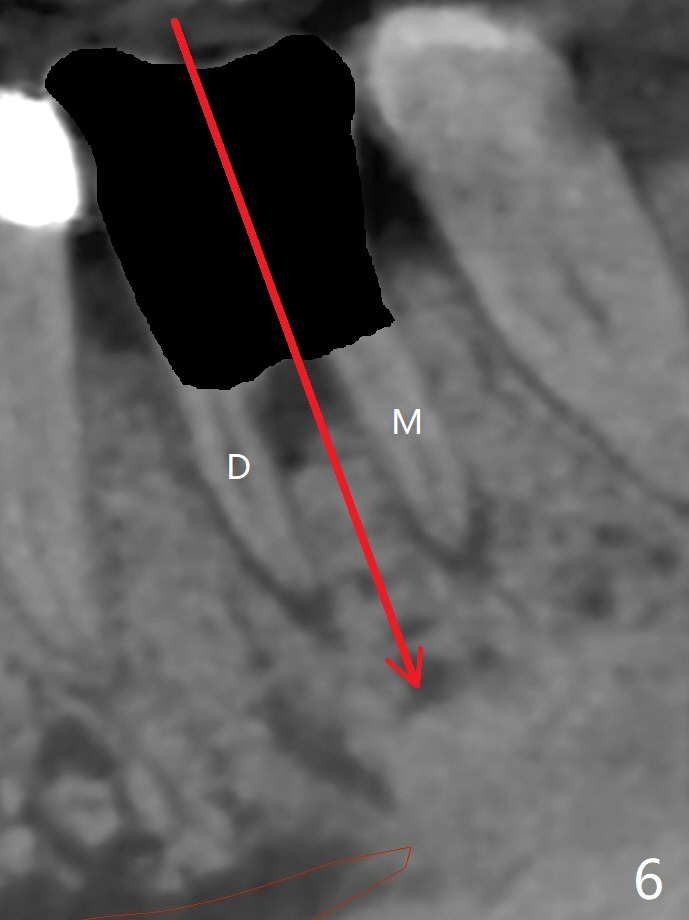

A 65-year-old man has nocturnal pain associated with #30 lingual furca caries and gingival recession (Fig.1,2). PRF (x2) and sticky bone will be used to repair the lingual soft and hard tissue defects. CT shows the submandibular fossa (Fig.3 <), dictating a short implant 10 mm, Fig.4). To place the implant in the septum (Fig.3 S), the coronal portion of the tooth is removed (Fig.5 black area) so that the roots are able to keep the osteotomy without deviation (Fig.6 red arrow). It is possible to place the implant in a trajectory mesiodistally (Fig.7 in fact after root extraction (arrows)). To prevent buccolingual deviation, a small implant (4 mm in diameter) is designed so that it will NOT touch the buccal (B in Fig.8) or lingual (L) plates. The bone density of the cortex and medulla is 2000 and 1400 units, respectively. To reduce the chance of implant fracture because of the narrow diameter in function, an implant with Titanium V will be used.